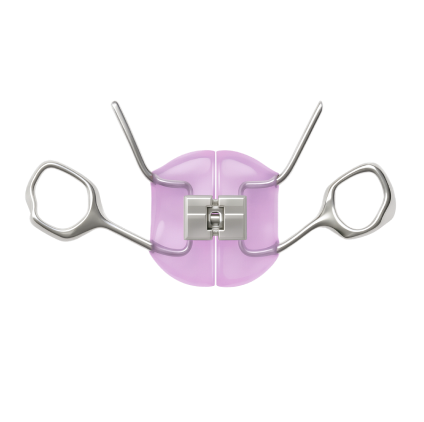

Протезы на имплантах

В этом случае в челюсть устанавливается несколько имплантатов, которые служат опорой для мостовидных протезов. Чаще всего врачи прибегают к протезированию all-in-2 (протез на двух имплантах, применяется только для нижней челюсти), all-in-4 или all-in-6 (протезирование на 4 и 6 имплантах, соответственно). Такой метод позволяет восстановить жевательную функцию и избавляет от неудобств, связанных с ношением съемного протеза.

Однако такой протез не защищает полностью от атрофии костной ткани, поскольку челюстная кость не будет испытывать жевательной нагрузки в зоне, где имплантов нет, и постепенно будет уменьшаться. Из-за этого протез через какое-то время потеряет плотное прилегание к десне и потребует перебазирования или замены.